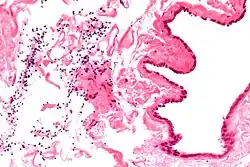

Micrograph of a spermatocele. The characteristic sperm are present (black dots - left of image). H&E stain. -

Dilated rete testis containing spermatozoa within cyst lumen. H&E stain 20x